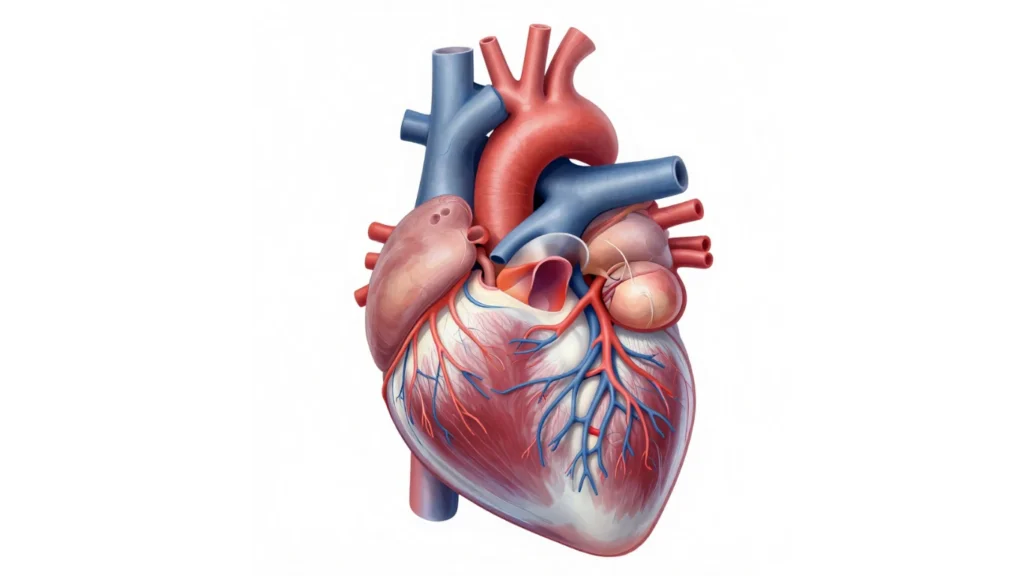

How Your Heart Works

Right side of the heart there is blood vessels called pulmonary arteries and these vessels moves blood from heart to the lungs.

Left side of the heart there is vessels called pulmonary veins so in the lungs blood gets oxygen and oxygen rich blood goes to the left side of the heart through vessels.

Then heart pumps the oxygen rich blood through the body’s main artery, called the aorta. So the blood goes to the rest of the body.

You just imagine, your blood is like a delivery truck carrying empty oxygen cylinders. It goes to the lungs to refill oxygen, then comes back full to supply the body.

Heart Valves

Four valves involves in the blood flowing to the right direction. these are

- Aortic valve

- Mitral valve

- Pulmonary valve

- Tricuspid valve

Note

Each valve has flaps, called leaf lets or cusps. The flaps open and close once during each heartbeat. If a valve flaps does not open or close properly then less blood moves out of the heart to rest of the body.